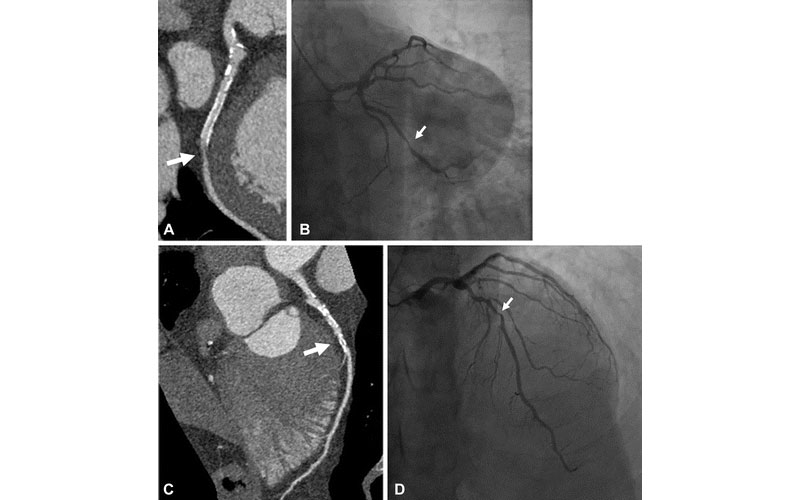

Case example of a 61-year-old man with history of myocardial infarction who was found at UHR-CT to have a severe (≥ 70%) stenosis in a large obtuse marginal branch of the left circumflex artery just distal to (A) a patent stent, which was confirmed at (B) invasive angiography. In addition, there was moderate disease noted by (C) ultra-high-resolution CT in the left main and in the mid left anterior descending artery (50%–70% stenosis), which was underestimated compared with (D) invasive angiography (70% stenosis). Arrow points to corresponding stenoses.

Latina et al. Radiology: Cardiothoracic Imaging 2021; 3(4):e210053 ©RSNA 2021